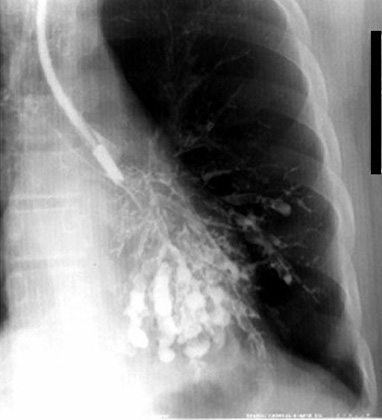

Хэсэг газрын уутанцар хэлбэрийн гуурсан хоолойн тэлэгдэл

Зүүн уушигны уг зүүн уушигны доод дэлбэн ателектаз болсны улмаас доош татагдсан байна. Зүрхний ард байрласан гуурс хэлбэрийн нягтрал (ялгаж харахад төвөгтэй ажээ). Бронхограммд уутанцар хэлбэрийн гуурсан хоолойн тэлэгдэл илэрсэн. Өнөө үед бронхограммын шинжилгээг ховор хийдэг болсон бөгөөд СТ сканаар онош тодруулах мэдээлэл авах боломжтой болжээ.

Бронхограмм

Зүүн уушигны доод дэлбэнгийн уутанцар хэлбэрийн гуурсан хоолойн тэлэгдэл.